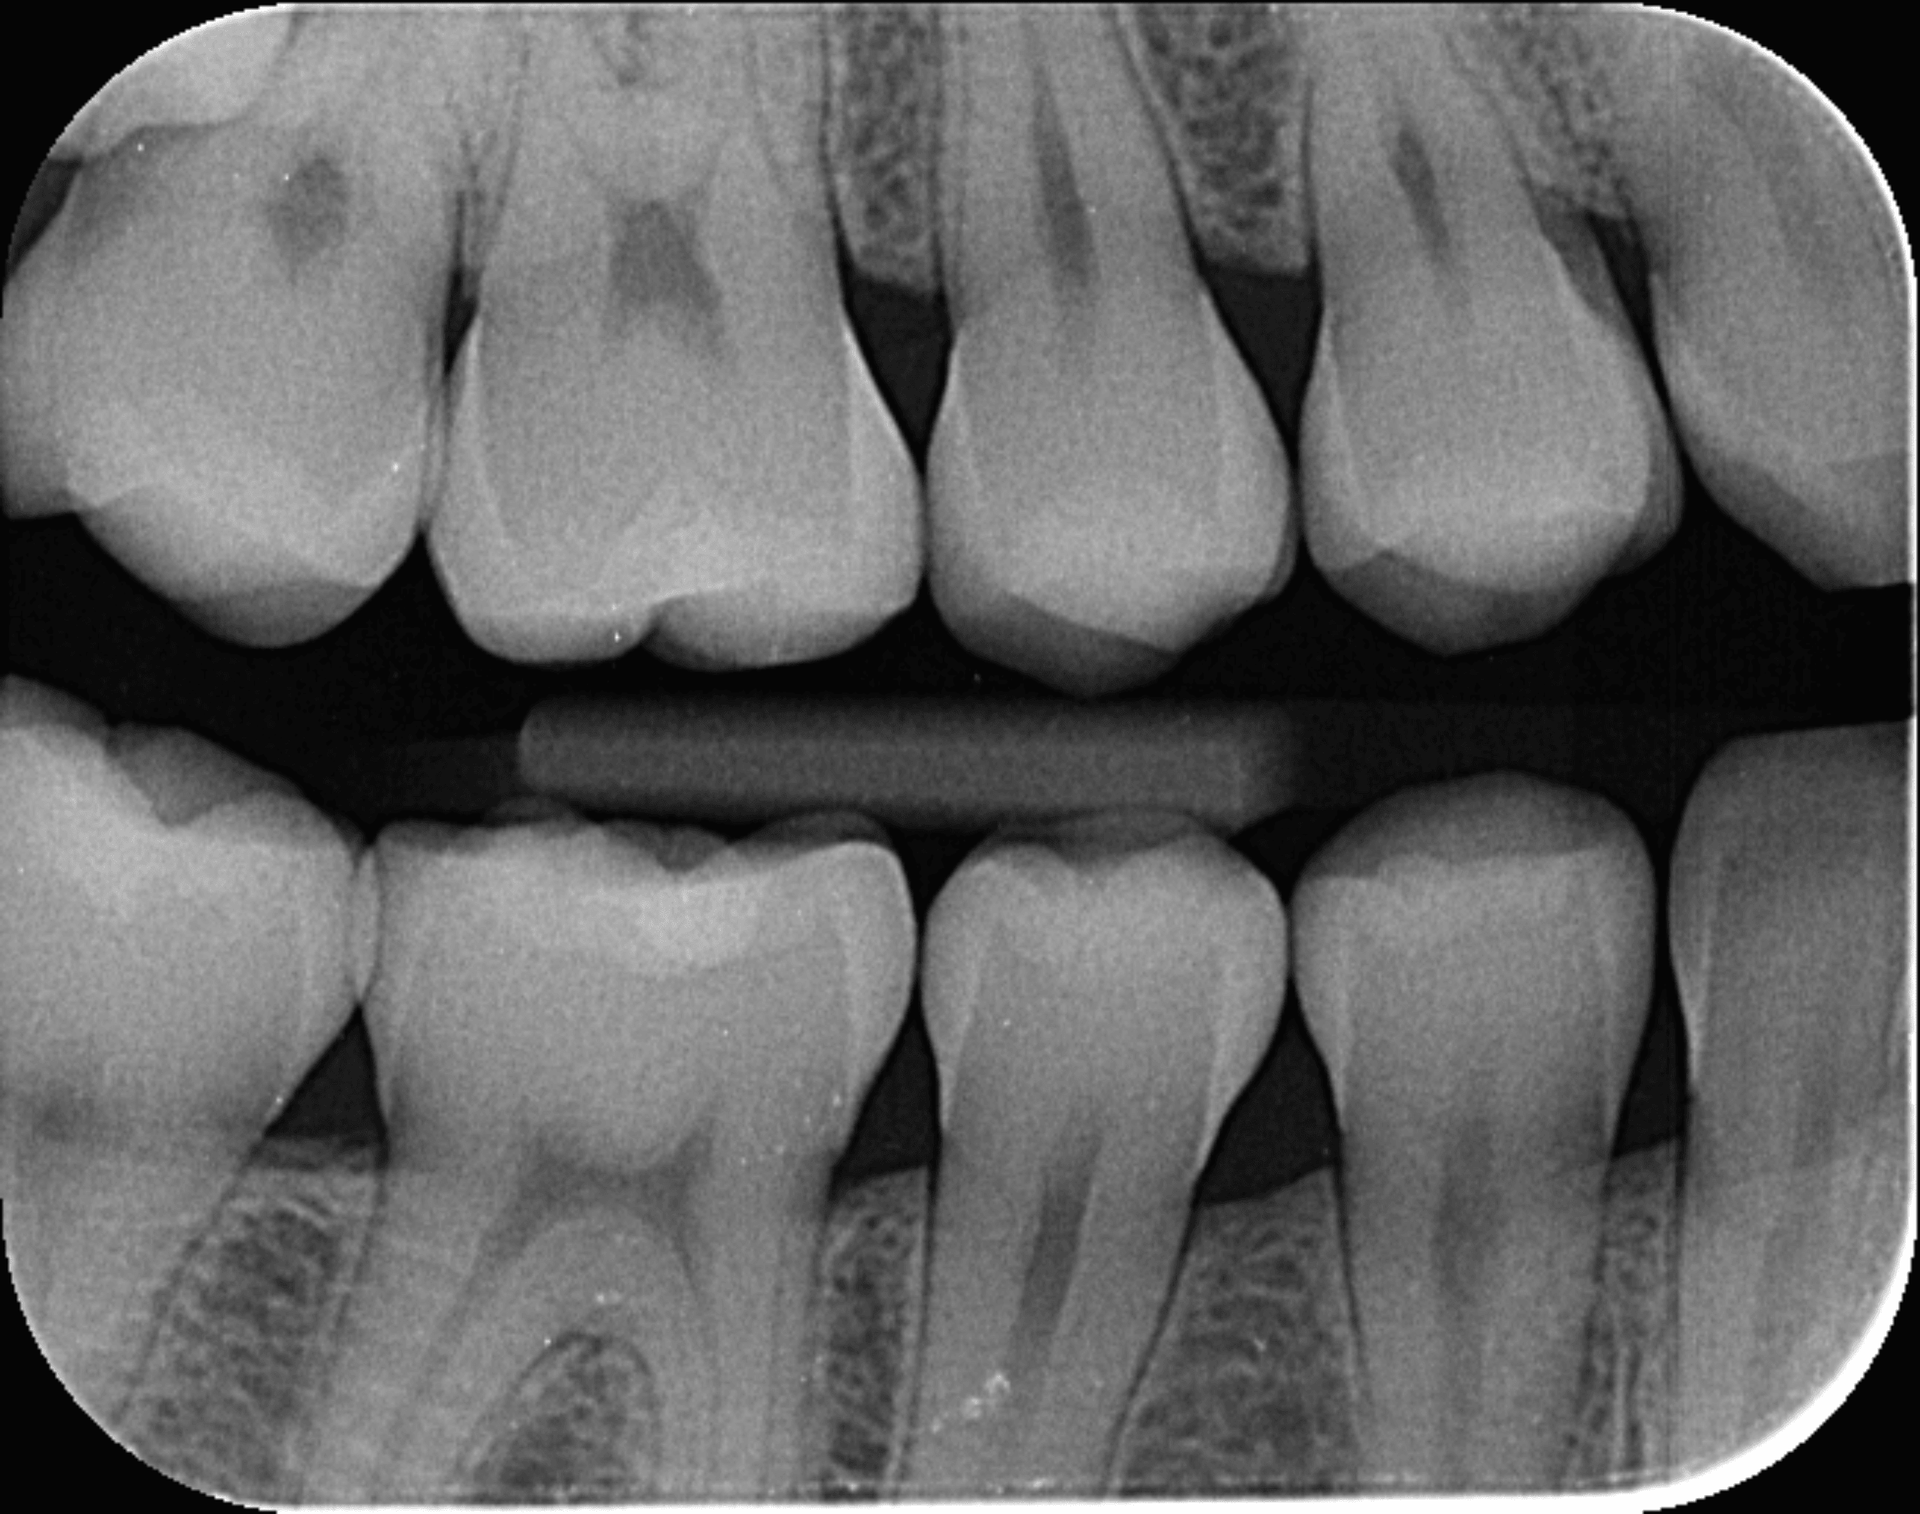

Unsere erfahrenen Zahnärztinnen setzen moderne digitale Röntgengeräte ein. So können aussagekräftige Röntgenbilder erstellt werden. Zudem profitieren Sie von einer deutlich geringeren Strahlenbelastung.